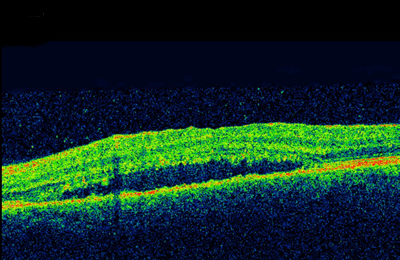

Figure 2.

Further dilated ophthalmoscopy examination of the retina revealed hyperaemic, swollen disc and multiple discreet yellow placoid patches of necrotising retinitis on the retinal periphery. On the temporal side, a few lesions extended within the vascular arcades. There were a few retinal haemorrhages, and patches of arteriolitis in the periphery (Figure 1). The right eye was quiet. Macular optical coherence tomography (OCT) demonstrated sensory macular detachment without any cystoid macular oedema (Figure 2). The fundus fluorescein angiography illustrated early hypofluorescence with delayed hyperfluorescence. There was no focal or diffuse leak in the macular area. He was otherwise fit and well.